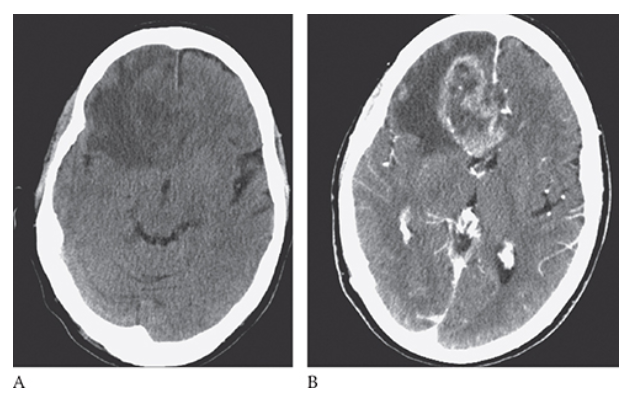

What is A

Glioblastoma Multiforme. shows an isointense mass with low-signal central necrosis and surrounding edema. Postcontrast T1W image

What is B

Glioblastoma Multiforme.hows peripheral irregular enhancement. FLAIR image

What is C

Glioblastoma Multiforme. shows high-signal edema.